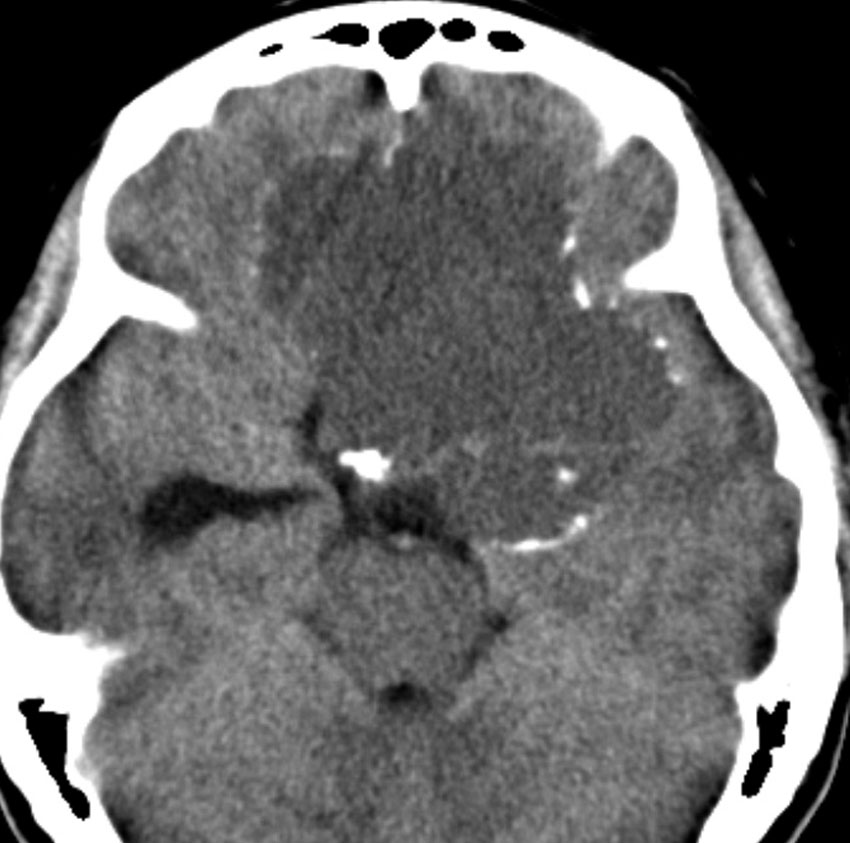

この子の症状は頭痛だけ。両親はなぜ気づかなかったのかと疑問を持ちますが,巨大になるまで症状が出ないこともあるのです。左のCTで腫瘍の周囲にバラバラと白い点状の石灰化があるので診断できます。左の視床下部から発生したクラニオでした。開頭手術しますが超高難易度です,怖いです (┯_┯) 複数回開頭手術になりましたが結果的に全摘出できています (by Dr 山本哲哉)。

嚢胞(液体が入っている袋)の部分と,腫瘍細胞が固まっている実質部分が入り交じっています。このくらいの大きさになってしまうと,下垂体機能を残すことはとても難しくなります。視神経が圧迫されて視力低下と視野障害を生じます。第3脳室が腫瘍で閉塞していて水頭症になっていますから知能の活動が低下します。

腫瘍を摘出するのに危ないのは,脳の血管の損傷です。左では白く,右では黒く線状に移っているのが太い脳動脈です。これら以外にもたくさんの細い重要な動脈が絡んでいます。

幸いこの患者さんの腫瘍は摘出できて患者さんは元気になりました。でもこのくらいのサイズになると手術がいつもうまくいくとは限りませんし重大な障害が残ることもあります。